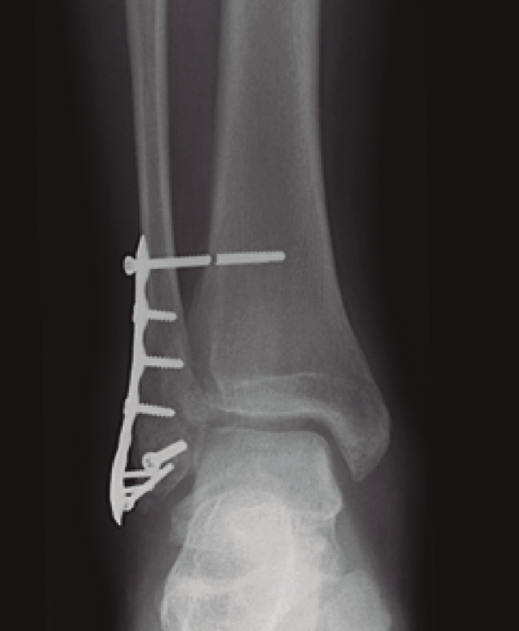

- Rotura o aflojamiento (Figura 2). Relacionada con no retirarlo, pero sin aparentes resultados negativos funcionales(15,16).

Figura 2. Fractura del maléolo peroneo sintetizada con placa anatómica y tornillo transindesmal roto a los 6 meses de seguimiento con mantenimiento de la reducción de la sindesmosis.